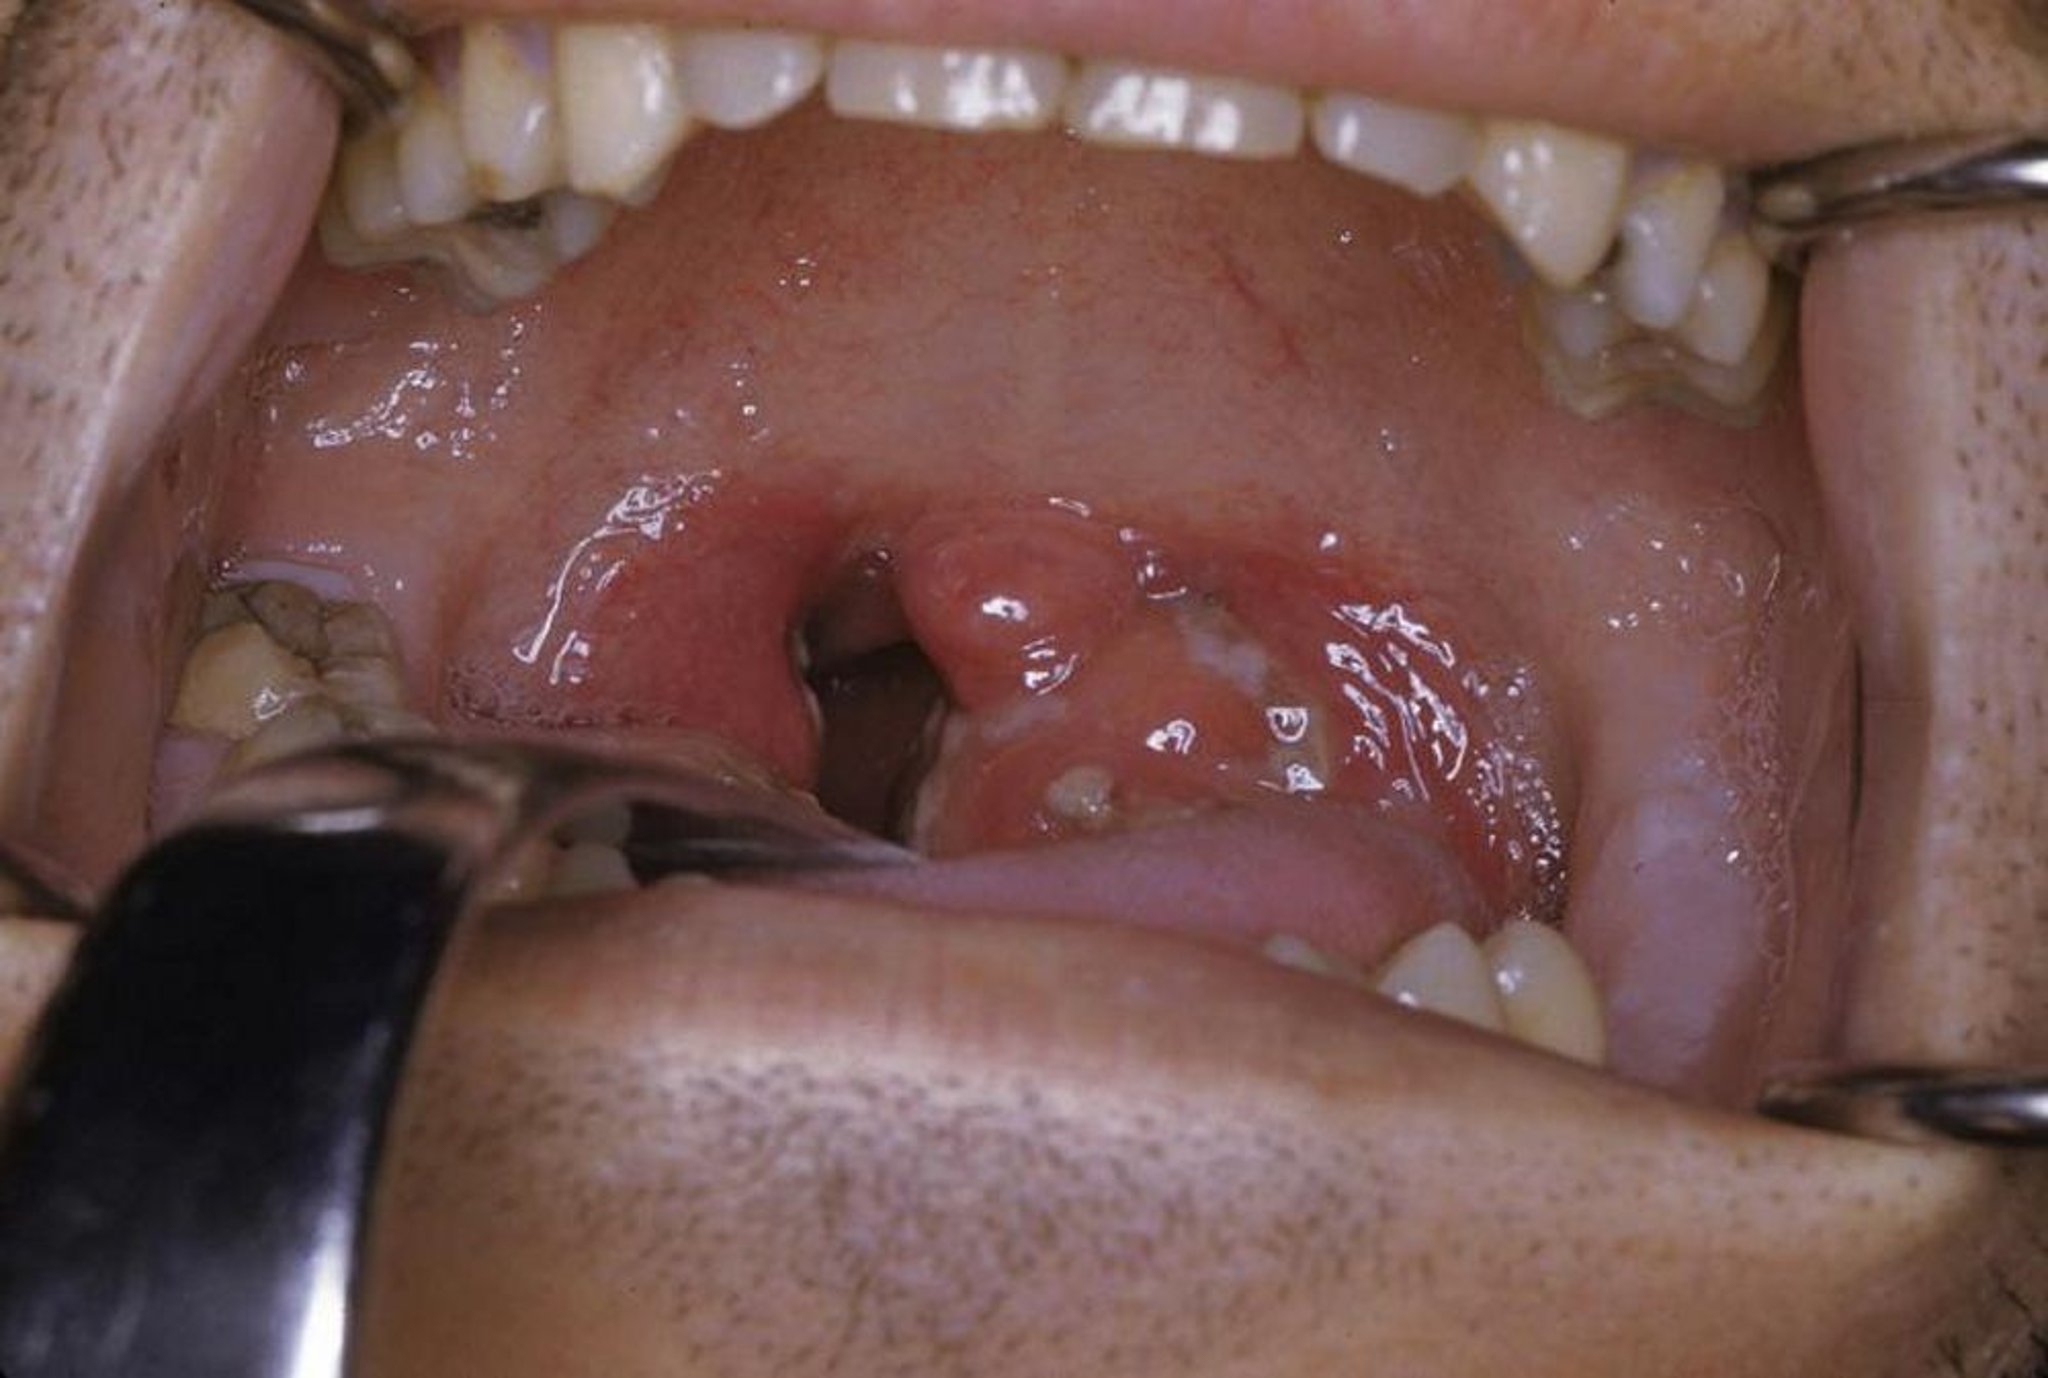

Dieses Foto zeigt eine akute Tonsillitis mit Exsudat und Erythem.

Foto zur Verfügung gestellt von Clarence T. Sasaki, MD.